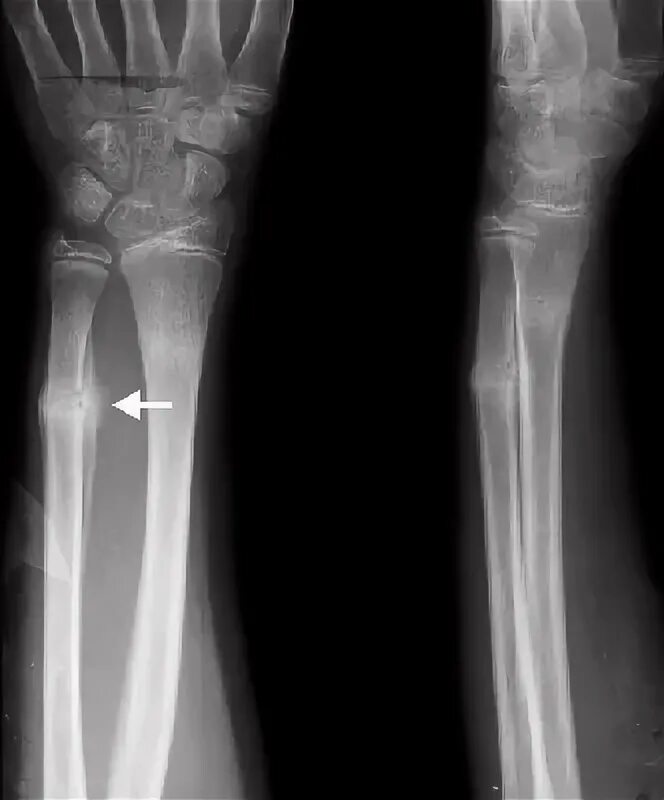

Чтобы быстрее сросся перелом руки